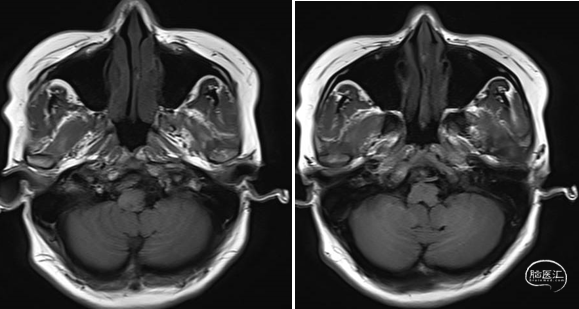

现病史:患者1周前于泰安市肿瘤防治院体检,颅脑MRI提示:跨枕大孔水平髓外椎管内占位,脊膜瘤可能性大。患者无头痛、头晕、恶心呕吐、意识丧失、肢体活动不利等症状,现患者为求进一步治疗就诊于我院,门诊以“椎管内占位”收入院。患者自发病以来神志清,精神可,饮食睡眠正常,二便如常,体重未见明显下降。

术前MRI